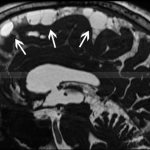

In order to analyze the contractility of the myocardial muscles, an ultrasound examination is performed. It also evaluates the size of the organ and the thickness of the heart chambers. To determine the degree of advanced disease, magnetic resonance imaging is prescribed.